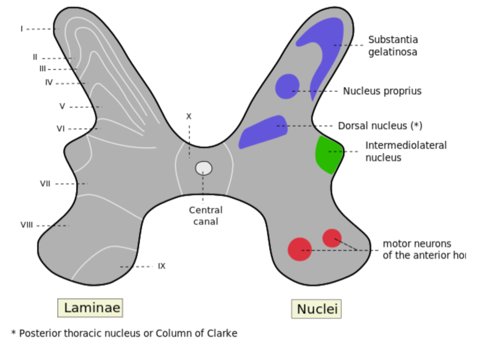

De olika fiber vi har dikuterat (Alfa-delta och C-fiber) kommer gå till ryggmärgen och till olika Lamina – vilket är uppdelingar av den grå substansen där 1 är mest dorsalt och 9 mest lateralt. Vad som går vad är:

- C-fiber till Lamina 1 och 2

- Alfa-delta till Lamina 1 och 2 (men även 5)

- Till IML kommer även signaler till Sympatiska fiber

- Signaler kommer via AlfaDelta eller C-fiber till lamina 1 via första-klassen-neuron

- I lamina 1 så kommer de kopplas om till ”andra klassen neroun” via synaps med Substans P om de är C-fiber, men Glutamat viket är snabbare om de är Alfa-delta fiber

- (i lamina 2 finns bara interneuron, den går alltså inte vidare här)